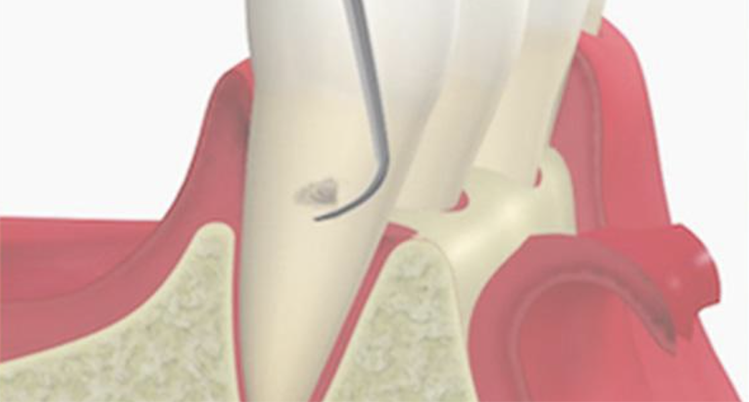

3. SRP

(スケーリング・ルートプレーニング)

専用の器具を使って、歯ぐきの中にある汚れを除去して、歯の根っこ部分の表面を汚れの付着が起こりにくい状態に仕上げる処置です。

主に、歯ぐきの中にまで歯石が入り込んでいる中等度以上の患者さまに対して行います。痛みが強い場合は、麻酔をして行うこともあります。